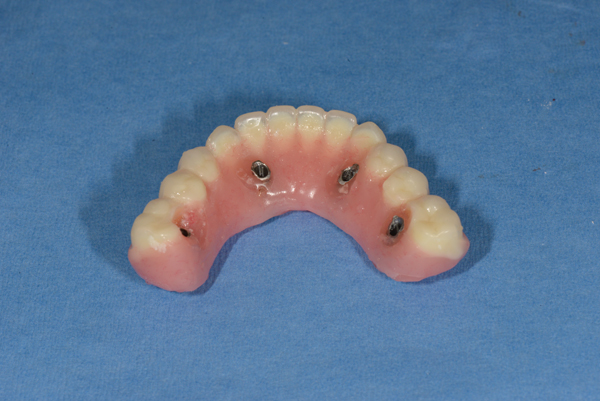

Fig 7. Sclar Center Protocol Provisional Prosthesis Guide used in surgical and restorative procedures. Treatment windows provide for restoration-driven implant placement and simplified restorative procedures.

Figure 7